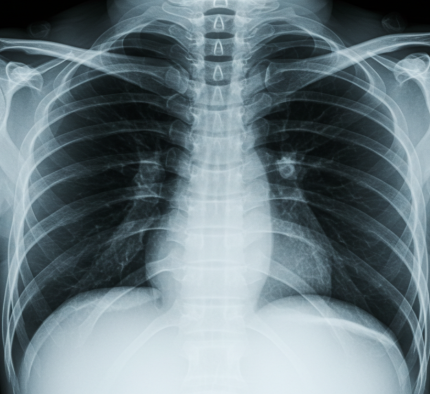

- 흉부 X레이: 폐까지 다쳤는지 추가 확인